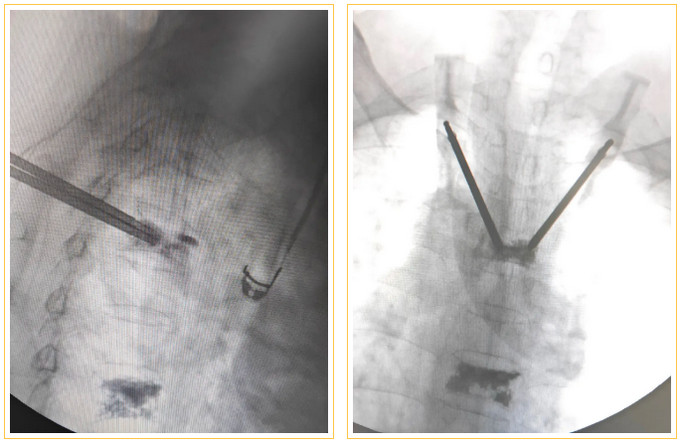

椎体成形术是一种脊柱微创手术,适合于骨质疏松性压缩骨折的治疗,皮肤切口仅2~3毫米,在X线透视引导下,通过穿刺针向骨折的椎体内注入“骨水泥”(一种骨科医用材料,由于它在凝固固化后外观和物理特性像建筑、装修用的白水泥而得名)将骨折的骨头粘合在一起,重建脊柱稳定性,达到缓解疼痛的目的,使患者早期恢复正常活动。

术中在细小的通道中穿刺打入骨水泥

面对如此高难度、高风险的手术,有着30多年骨科临床工作经验的王荣茂、林翔主任医师,在做足了充分的术前准备后,带领团队刘蔚楠、林家钟博士等迎难而上。他与手术室、麻醉科密切配合,在陈磊麻醉医师干脆利落的麻醉下,仅用时20分钟就顺利为陈阿姨完成手术。

林翔主任为患者进行手术